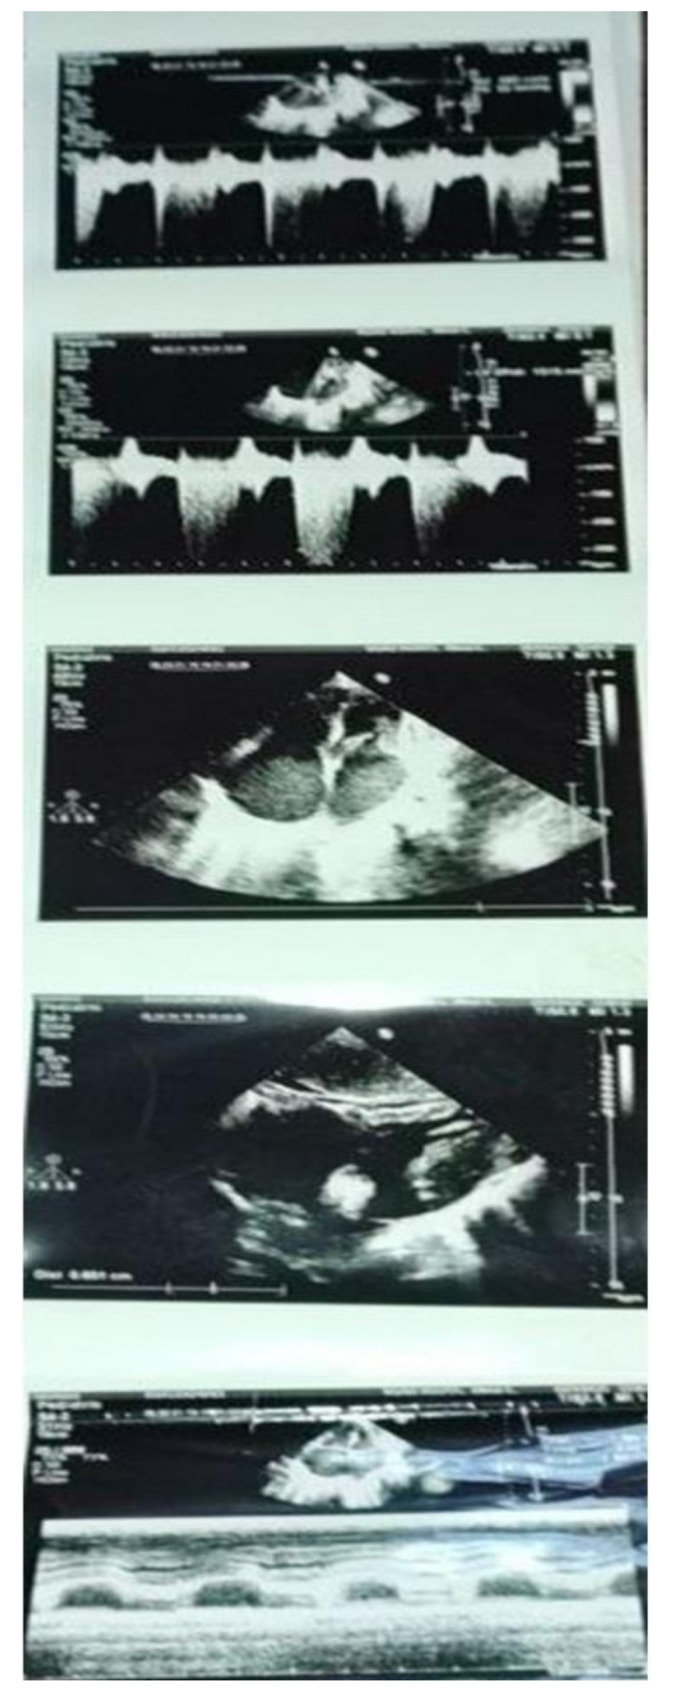

Results: The c.406 C > T variant, classified as likely pathogenic, results in a truncated TNNI3 protein. Bioinformatics analysis highlighted significant structural disruptions, likely impairing sarcomere function. The patient presented with growth retardation, progressive dyspnea, and echocardiographic findings consistent with RCM. Both parents were heterozygous carriers, supporting an autosomal recessive inheritance pattern. The homozygosity of the novel variant identified in this study is a critical factor in the genotype-phenotype correlation observed in this case.